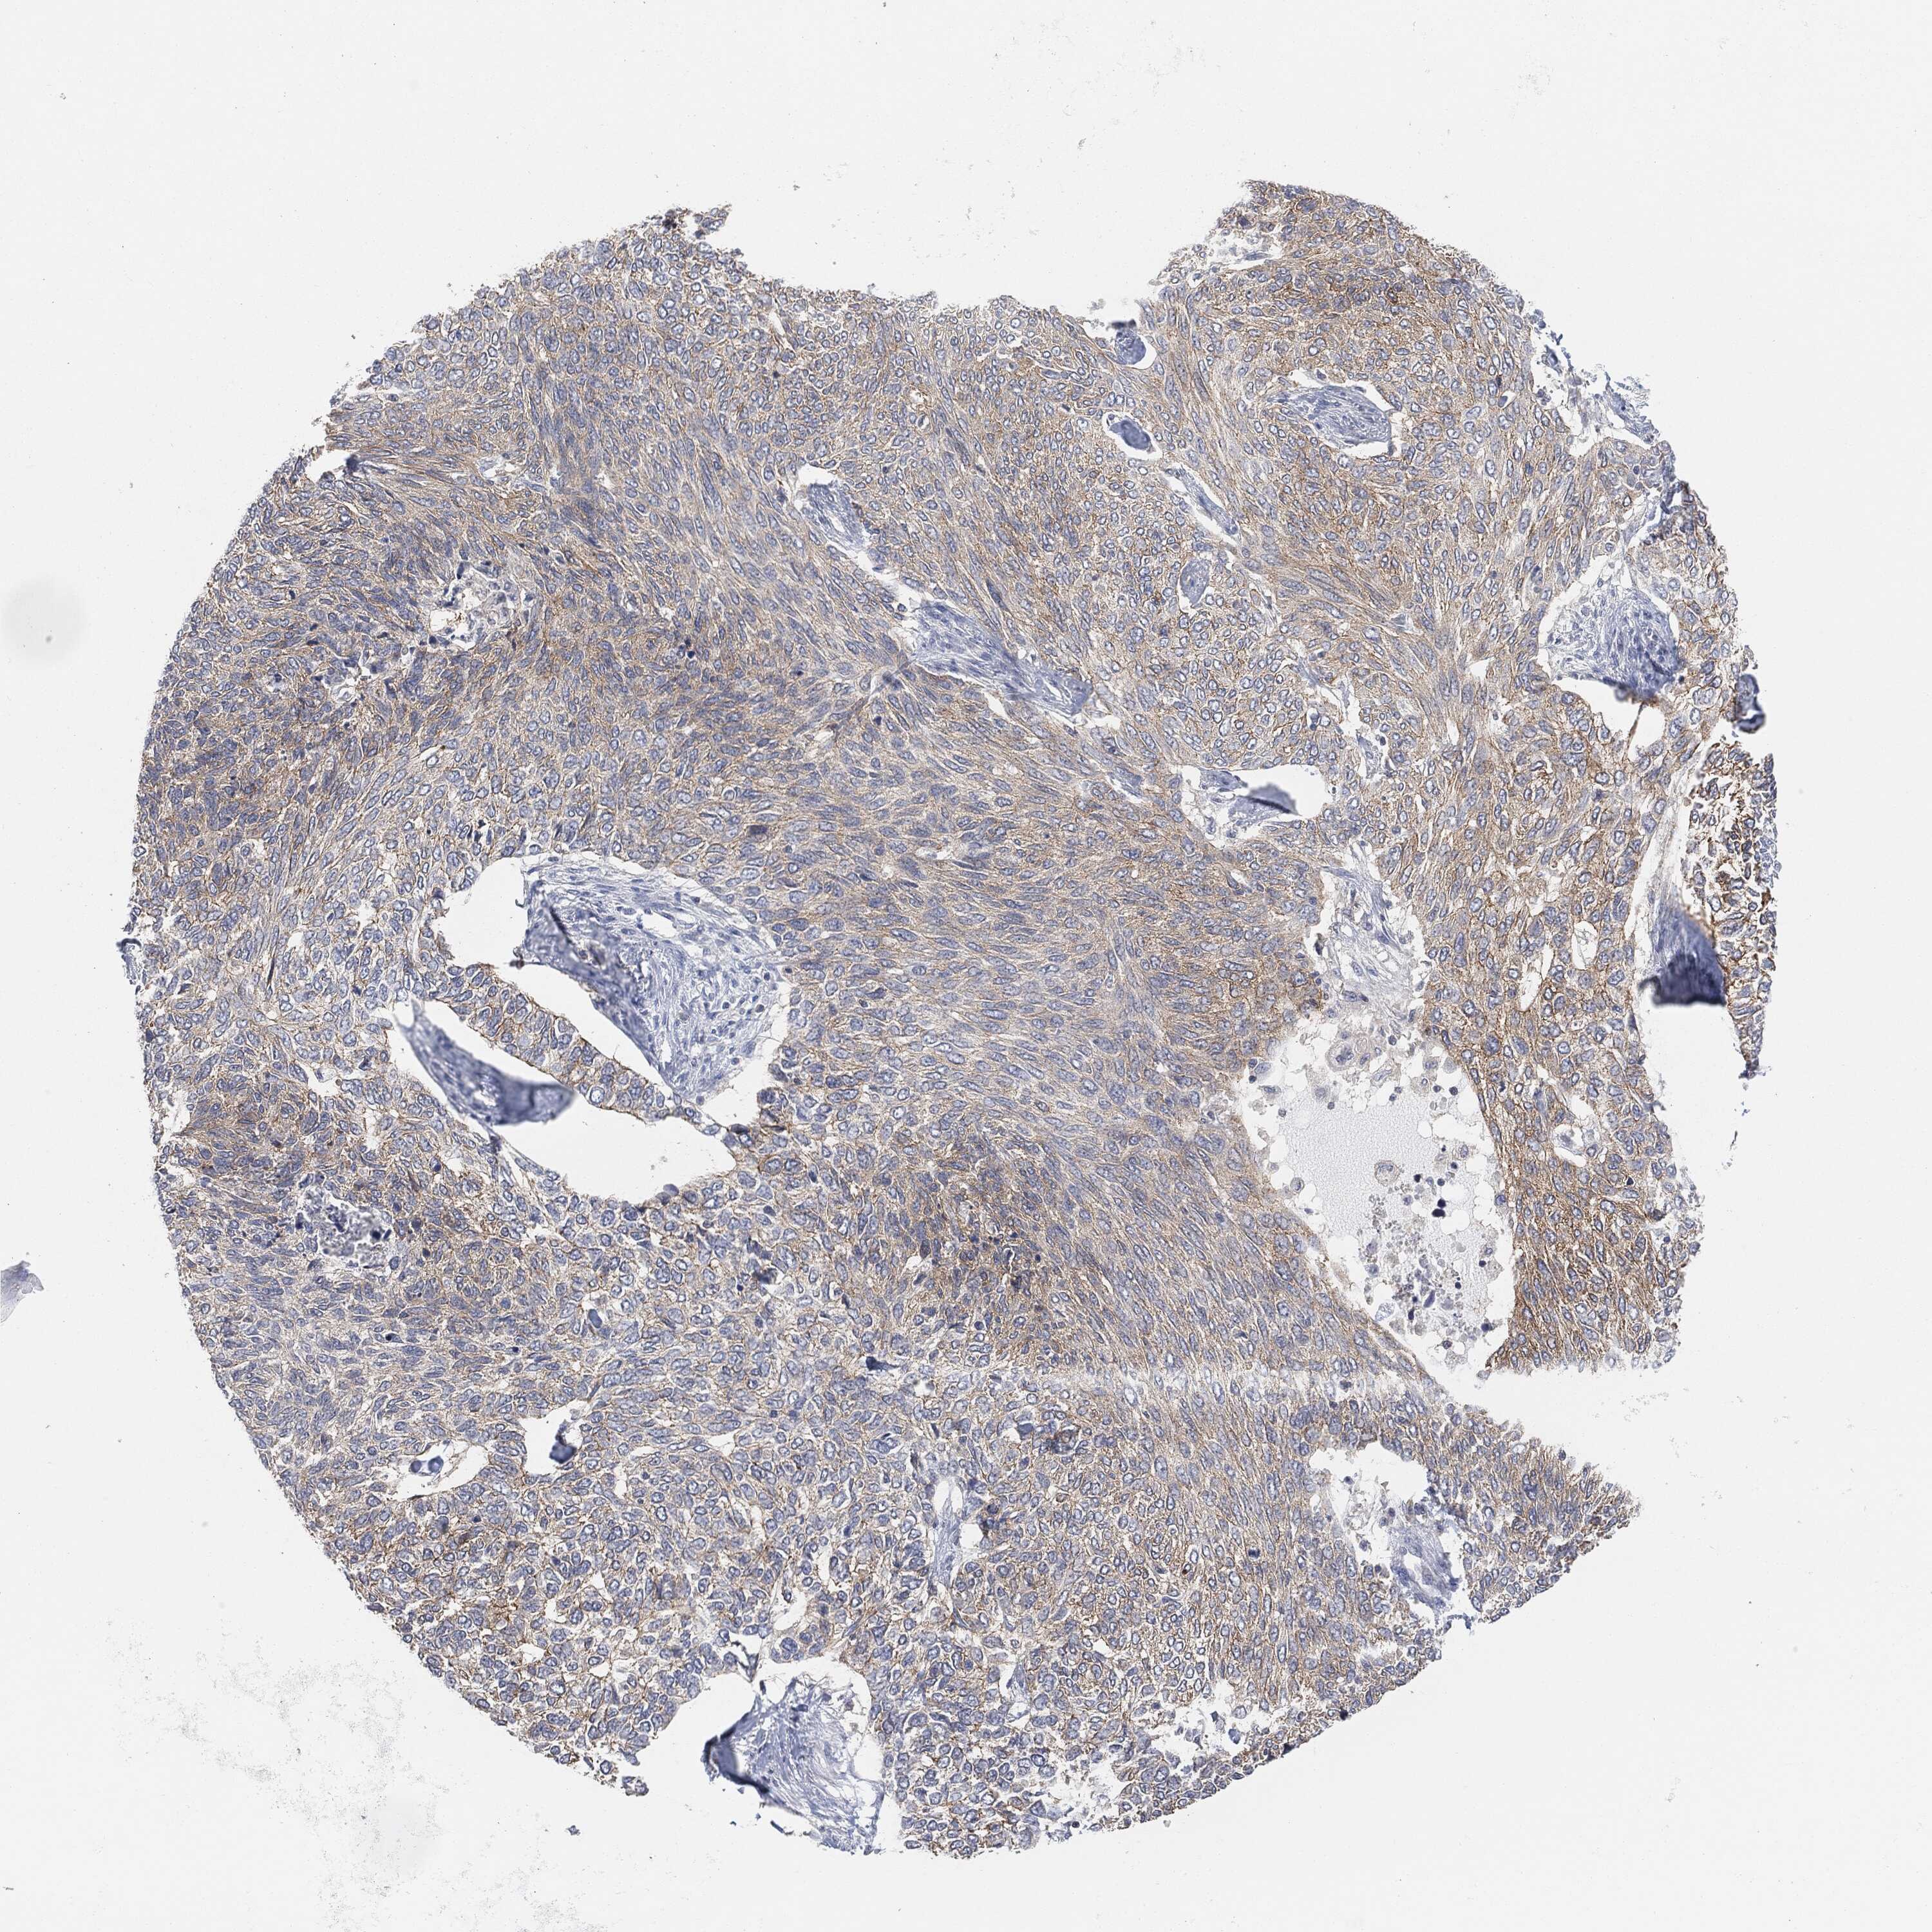

SKIN CANCER - Protein expressioni

A mouse-over function shows sample information and annotation data. Click on an image to view it in a full screen mode. Samples can be filtered based on level of antibody staining by selecting one or several of the following categories: high, medium, low and not detected. The assay and annotation is described here.

Each image is clickable and will lead to virtual microscopy that enables deeper exploration of all samples and also displays staining intensity scores, fraction scores and subcellular localization as well as patient and tissue information for each sample.

Staining

High

Medium

Low

Not detected

Intensity

Strong

Moderate

Weak

Negative

Quantity

>75%

75%-25%

<25%

None

Location

Nuclear

Cytoplasmic/membranous

Cytoplasmic/membranous,nuclear

Squamous cell carcinoma, NOS